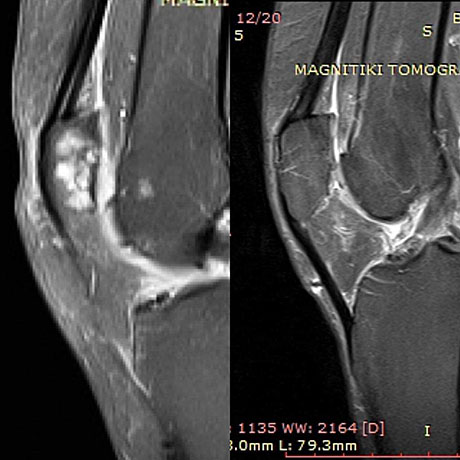

Woman 59 years old with severe damage of the patellar articular cartilage. Autologous bone marrow stem cells with collagen (AMIC technique), before and two years postop

The same patient.